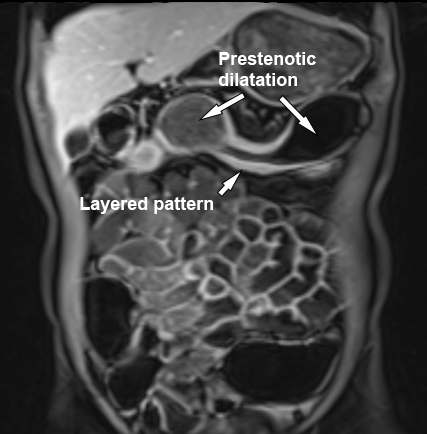

Ruột non đang viêm với dày thành và tín hiệu T2W thành ruột nhẹ (mũi tên) trên hình ảnh T2 axial có fat-sat. Có thể thấy giãn trước hẹp ở phía trên đoạn ruột bệnh lý.

Cường độ tín hiệu T2W thành ruột có thể được phân độ như sau khi sử dụng chuỗi xung T2 có fat-sat:

- Không tăng

thành ruột bình thường - Tăng nhẹ

thành ruột có màu xám đậm - Tăng vừa

thành ruột có màu xám nhạt - Tăng nhiều

thành ruột chứa các vùng tín hiệu cao màu trắng, gần bằng tín hiệu của nội dung lòng ruột.